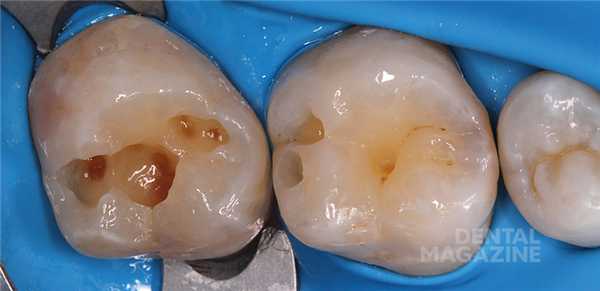

Внешний вид окклюзионного ключа показан на рисунке 4 .

Далее осуществляют препарирование и адгезивную подготовку системой XP Bond™ на основе терт-бутанола (рис. 5) .